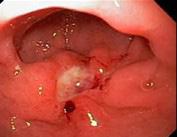

Figura 31. Colonoscopia. Se puede observar una mucosa pálida y una pérdida del patrón vascular. Estos hallazgos son compatibles con la colitis isquémica.

Compromiso del intestino grueso o colitis isquémica: la causa más común es por shock hipovolémico (Ej,. en politraumatizados o gran quemados). Generalmente ocurre a nivel del colon izquierdo (colon descendente y ángulo esplénico). El paciente suele referir dolor en flanco izquierdo asociado con signos de shock hipovolémico. El diagnóstico es por colonoscopia. Eventos crónicos: